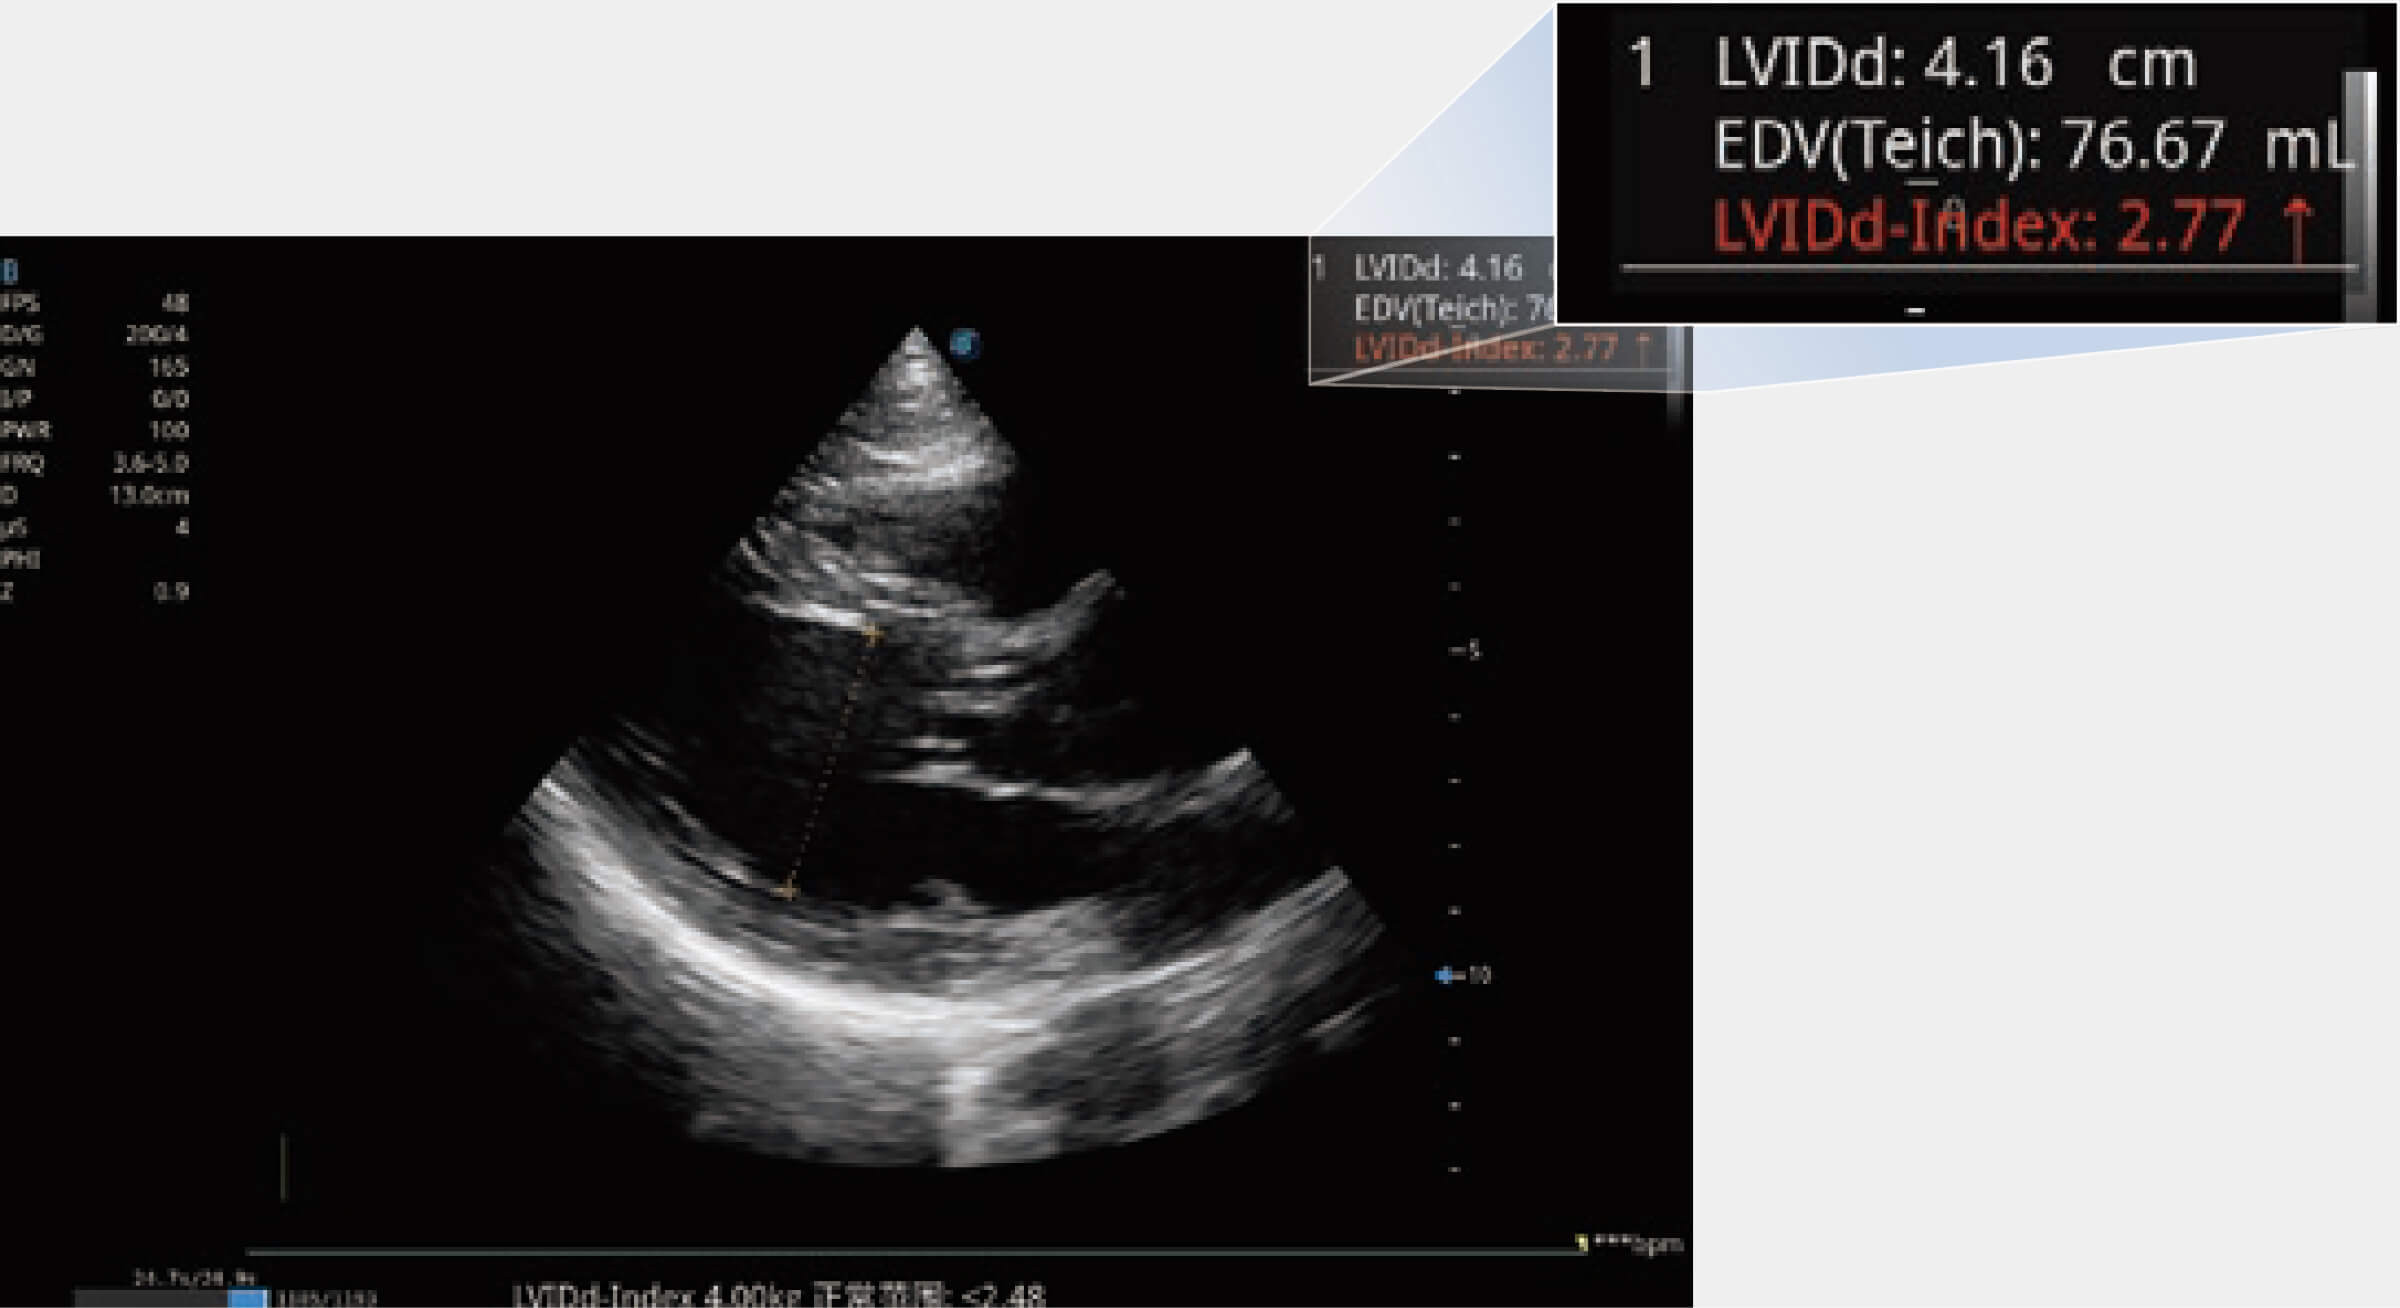

當(dāng)心臟測(cè)量結(jié)果超出正常范圍時(shí),可實(shí)時(shí)預(yù)警提示動(dòng)物醫(yī)生,減少疾病漏診概率。

ProPet 80 配備了豐富的心臟探頭群、先進(jìn)的成像技術(shù)和專(zhuān)業(yè)的心臟測(cè)量工具,可幫助動(dòng)物醫(yī)生為不同體型和生理結(jié)構(gòu)的動(dòng)物提供心臟和心肌功能的全面評(píng)估。